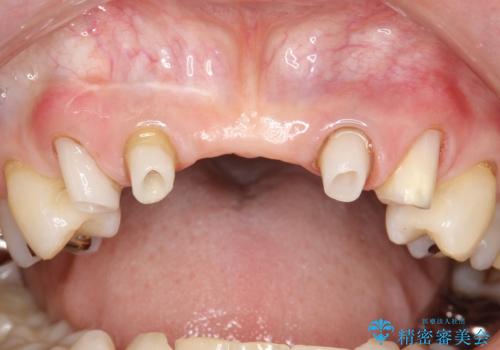

前歯のブリッジの見栄えが悪い→見えないところからしっかりとやり直しを

- 仮歯の製作、古い土台(メタルコア)の除去まで行い、根管治療は専門医に依頼

→根管治療終了後、ファイバーコアを築造し、新しいセラミックブリッジを製作した。

一見きれいにはいっているセラミックも、はずして中の状態をみるとひどいことが多い。これは、中の土台の状態や処理のクオリティは、短期的には問題を起こしづらく、患者さんには見えない部分だからです。